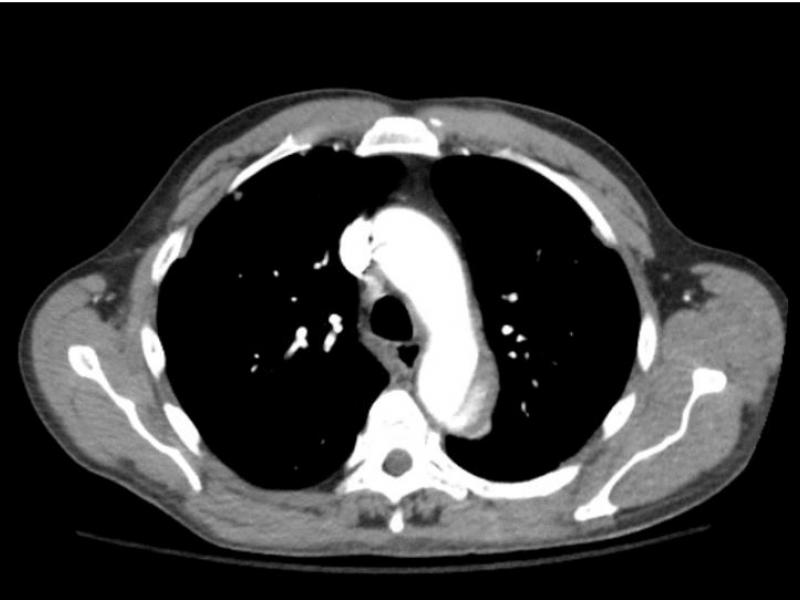

A 70 yo M w/ a PMHx of HTN and DM presents to the ED with